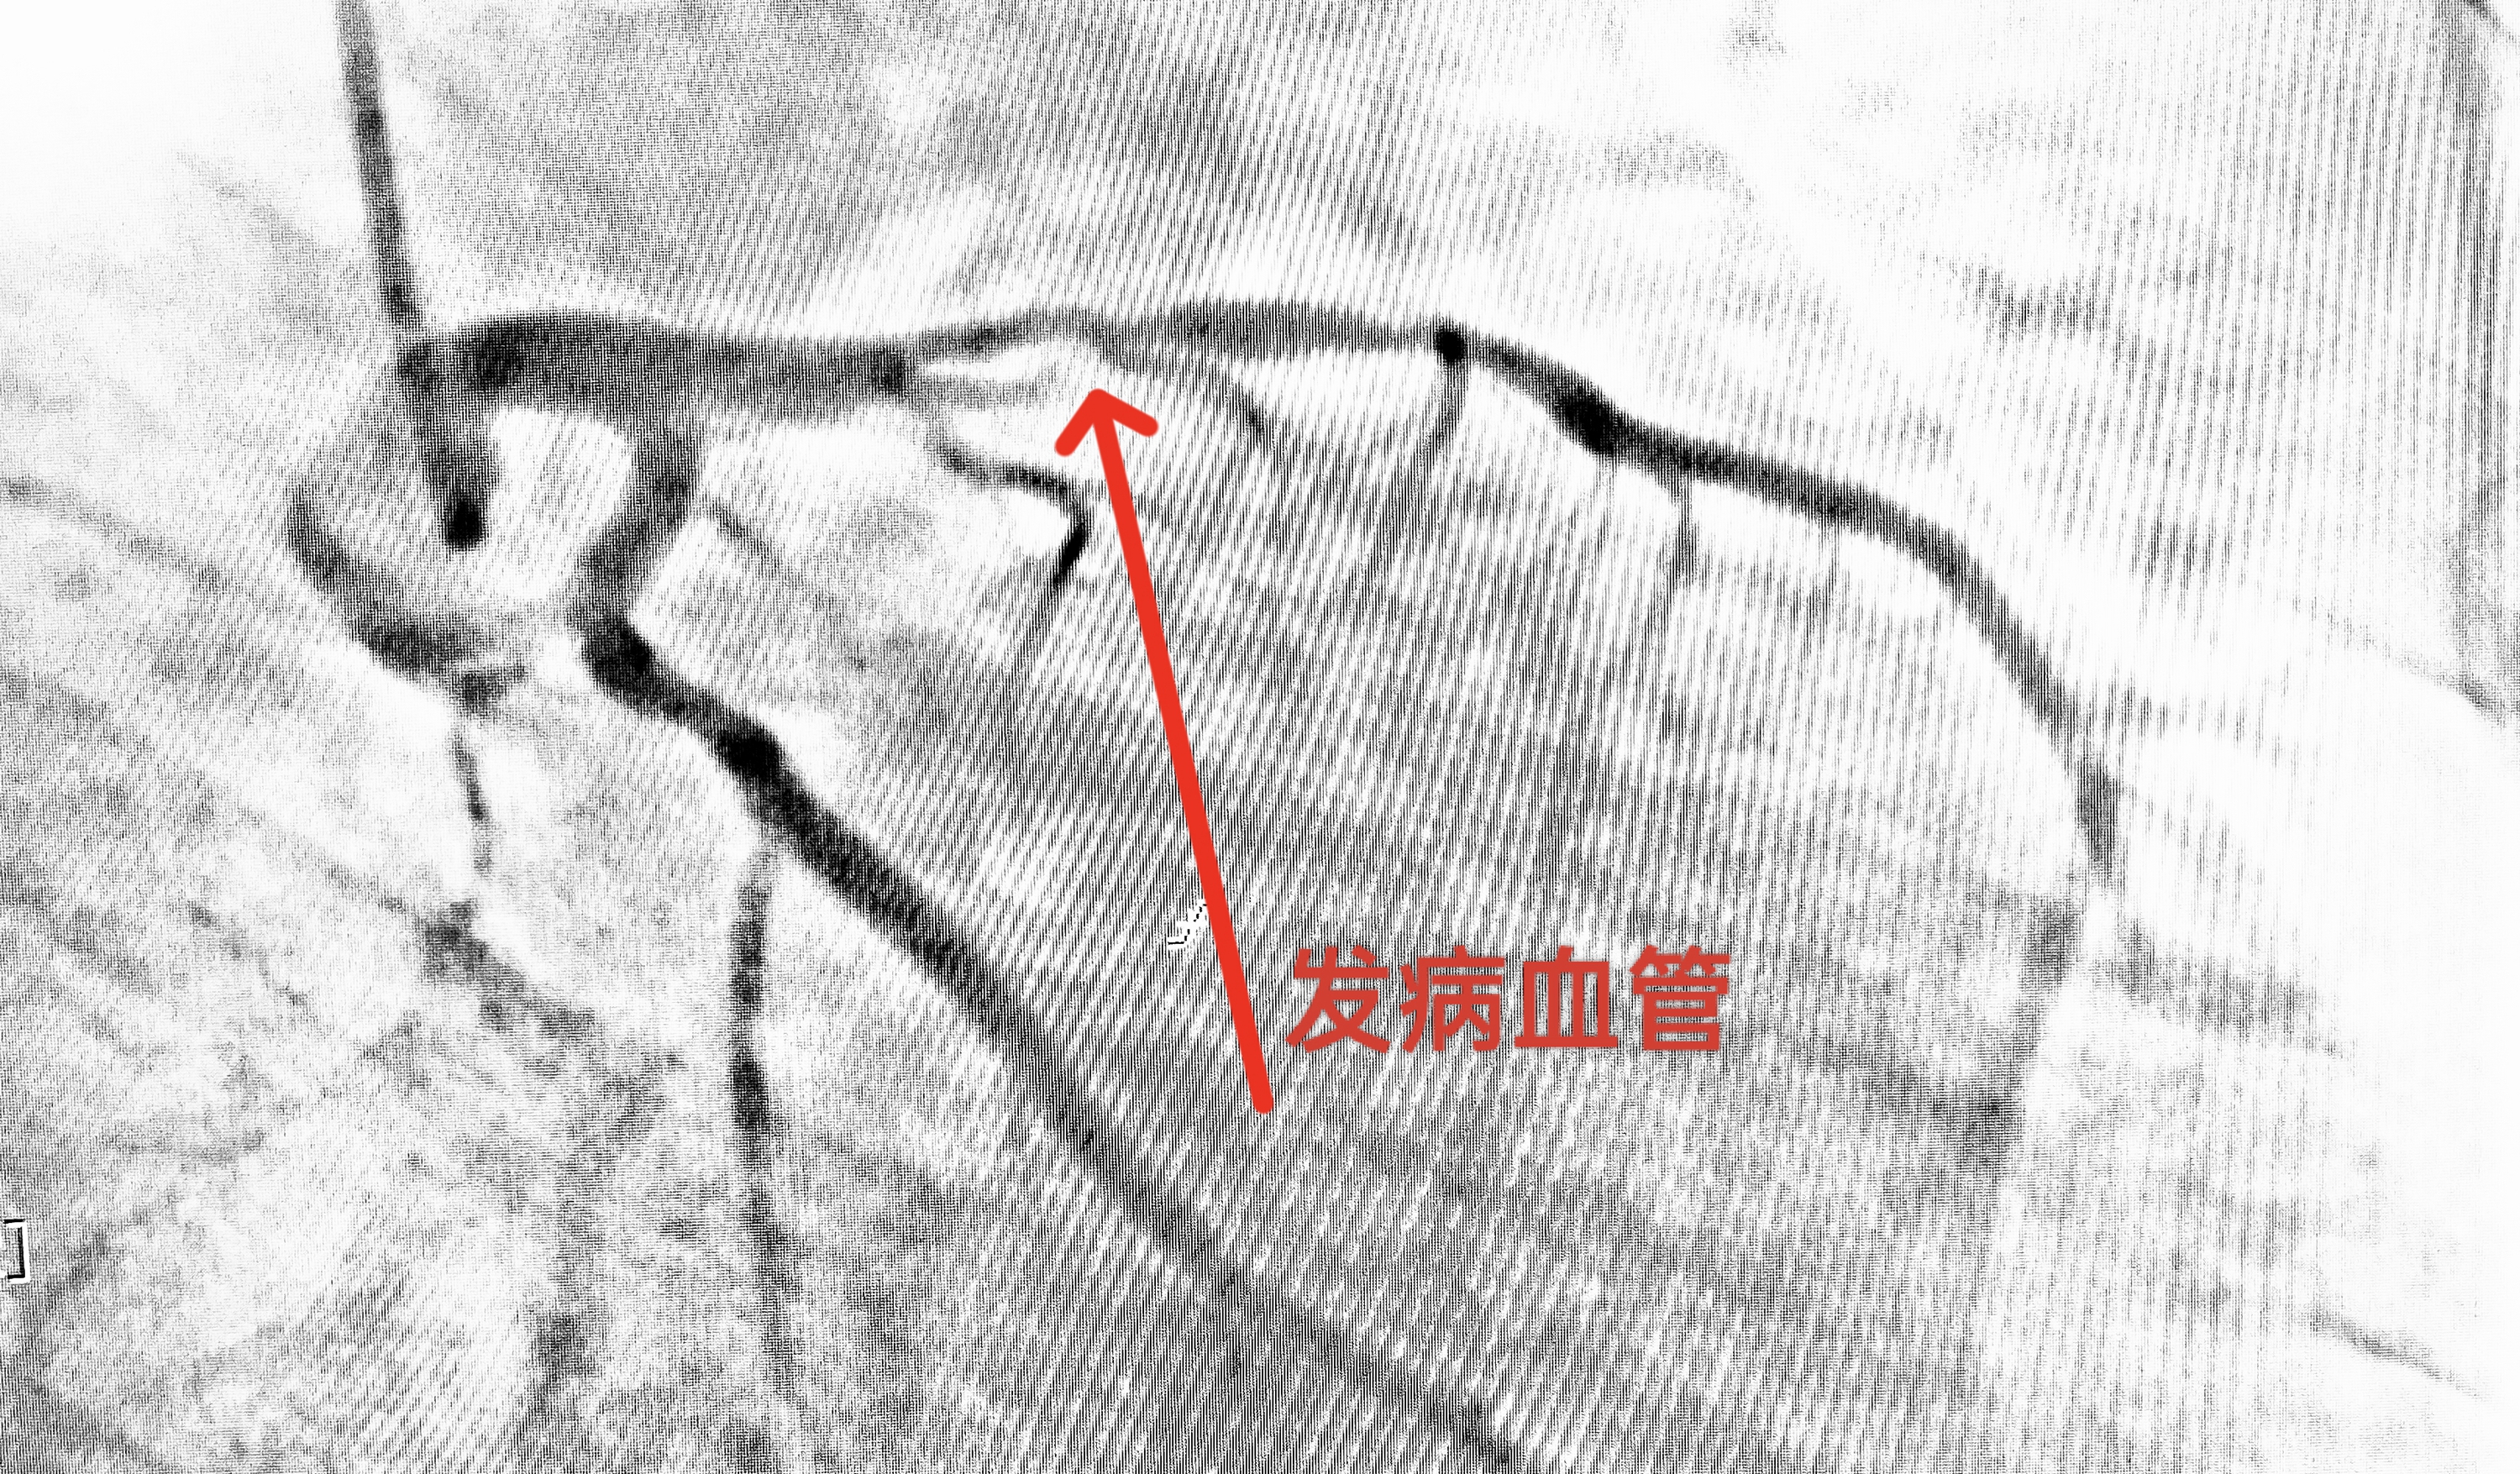

介入中心团队10分钟到达导管室开展紧急救治,经过了40分钟的精准手术,我院心血管内科介入团队开通了患者前降支近端狭窄95%的血管,顺利植入支架。术后,患者病情稳定,转入病房继续密切观察。